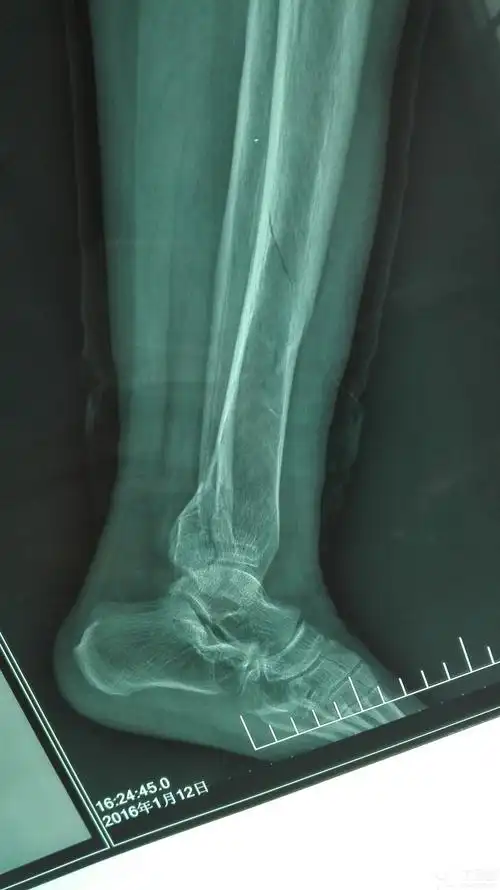

胫骨螺旋形骨折,外踝骨折,后踝骨折 - 骨科专业讨论版 -丁香园论坛